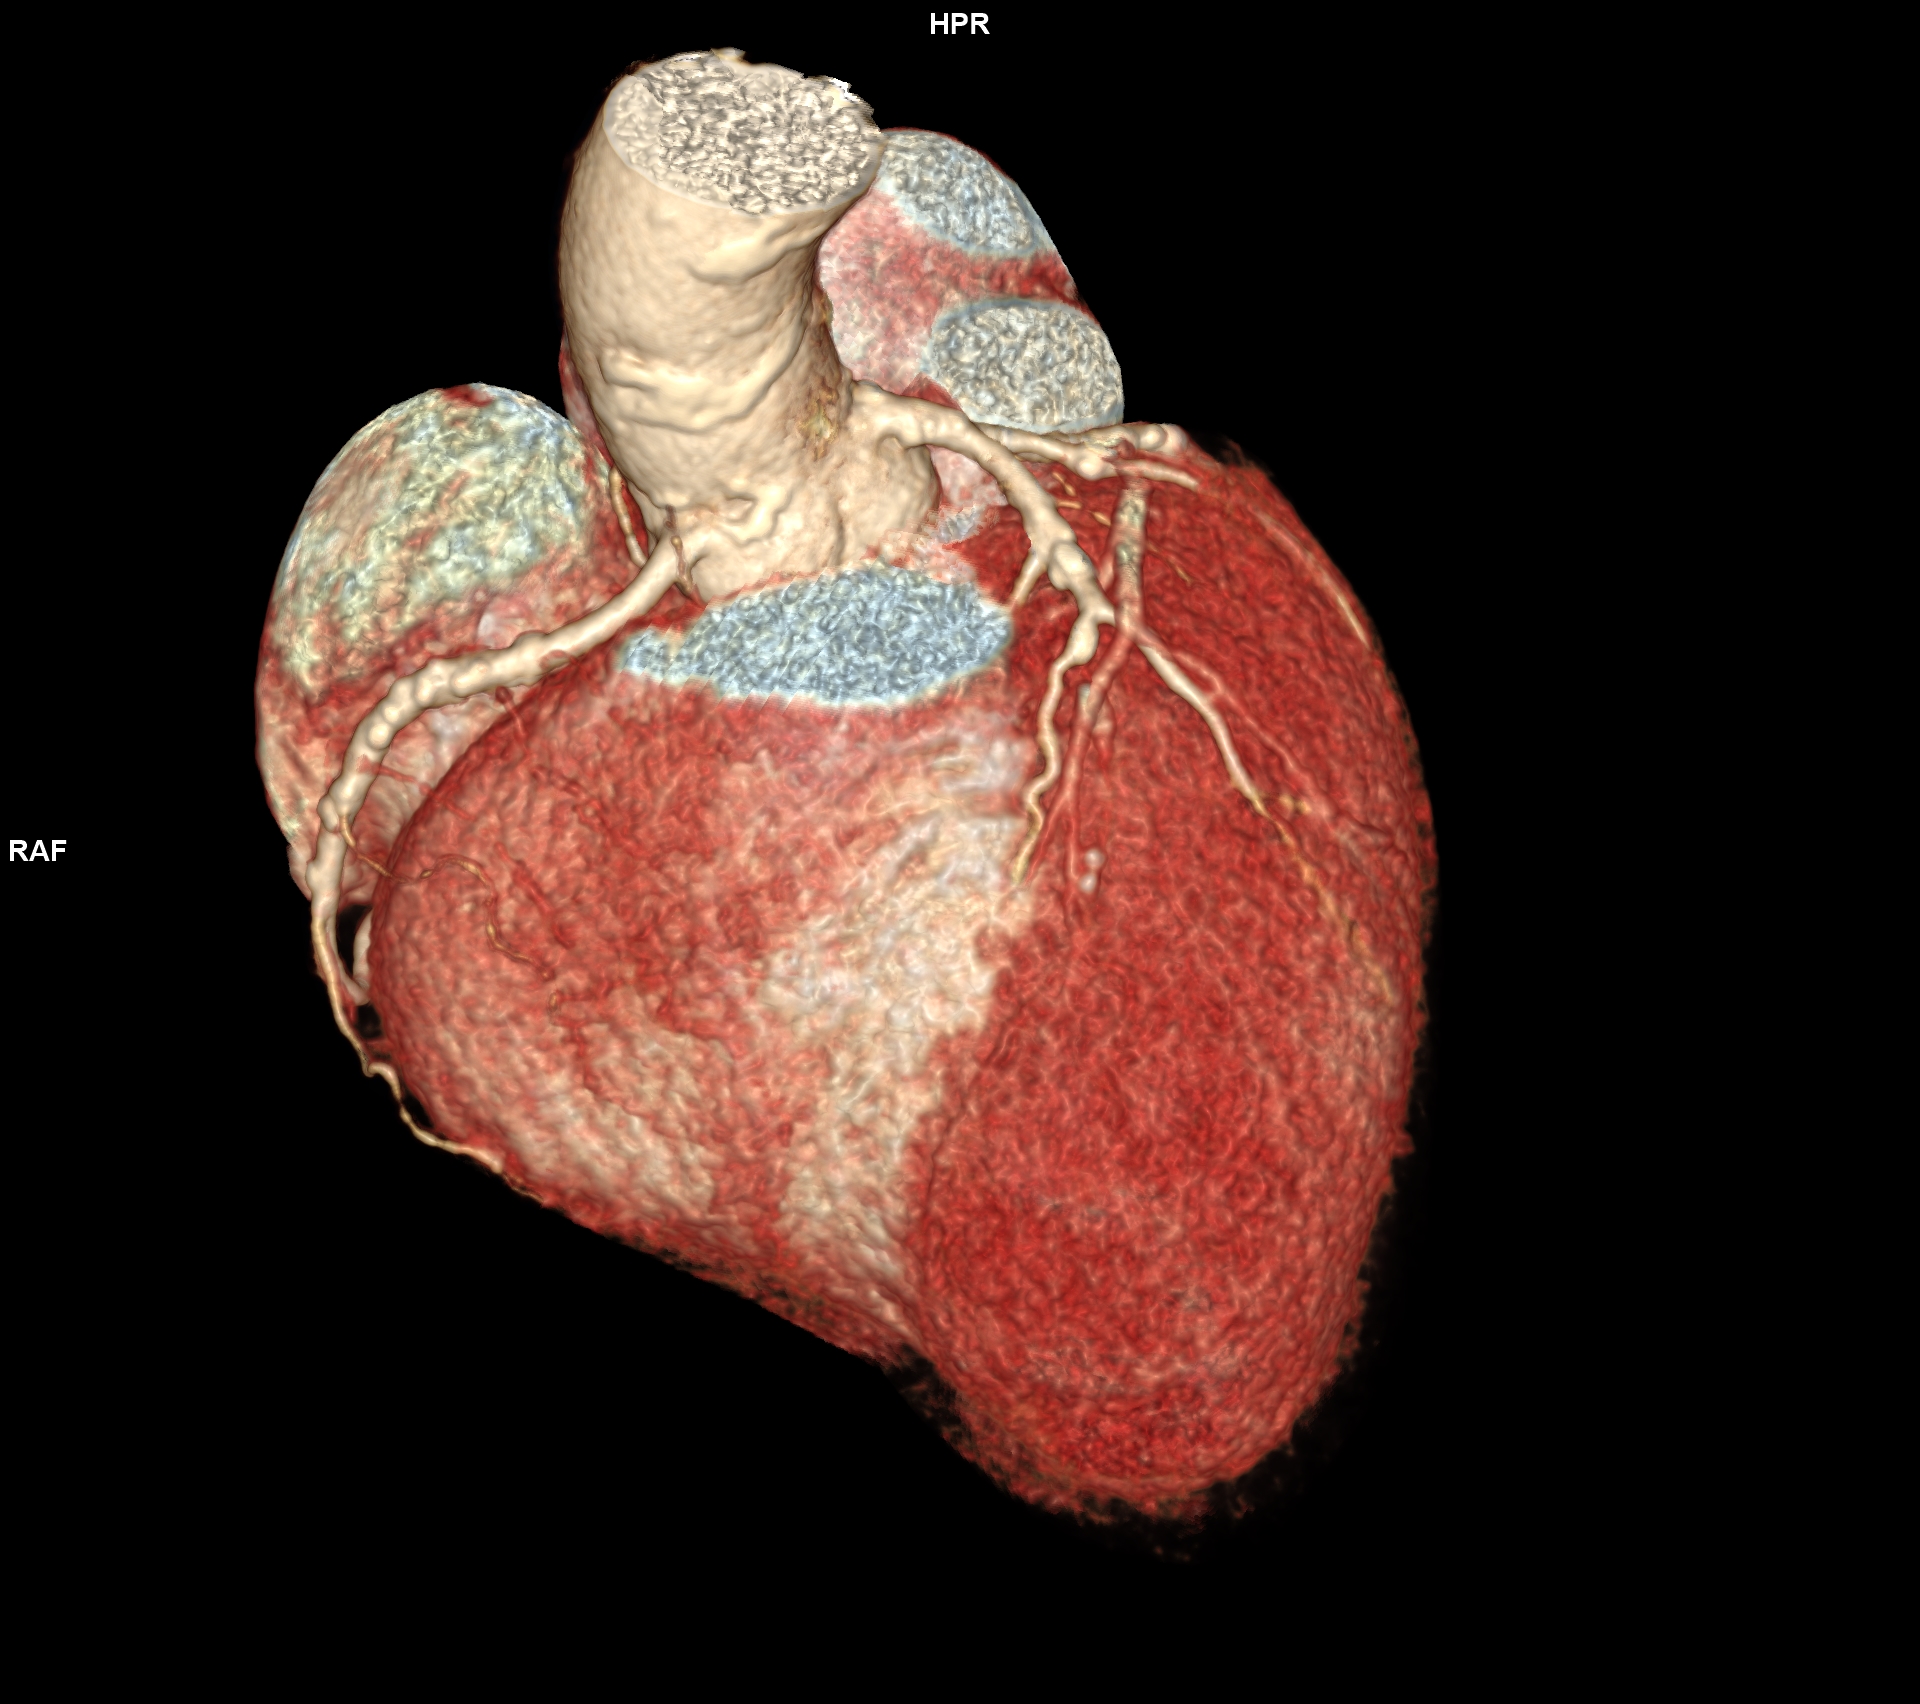

Figura 2: reconstrucție volumică din achiziție angioCT coronariană cu sincronizare ECG

Discuţie caz nr 120: Achiziția angioCT coronariană cu sincronizare ECG evidențiază ocluzie a arterei descendente anterioare în segmentul mediu cu hipokinezie severă / diskinezie a miocardului deservit și formarea unui anevrism antero-septal și apical ventricular stâng ce este locuit de un tromb.